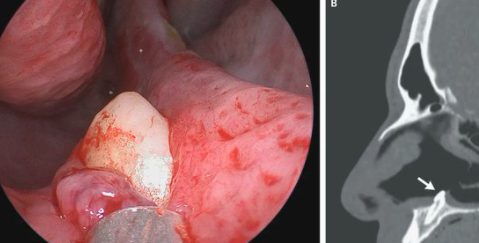

Los médicos quisieron indagar un poco más y, tras introducir una cámara, se toparon con una "masa blanca, dura, no dolorosa", visible sobre la superficie de la base de la fosa nasal. Finalmente, una tomografía computarizada confirmó que se trataba de un diente que había crecido fuera de sitio.

Los médicos optaron por una simple extracción mediante cirugía. Una vez retirado el diente, confirmaron su tamaño: 14 milímetros de largo.